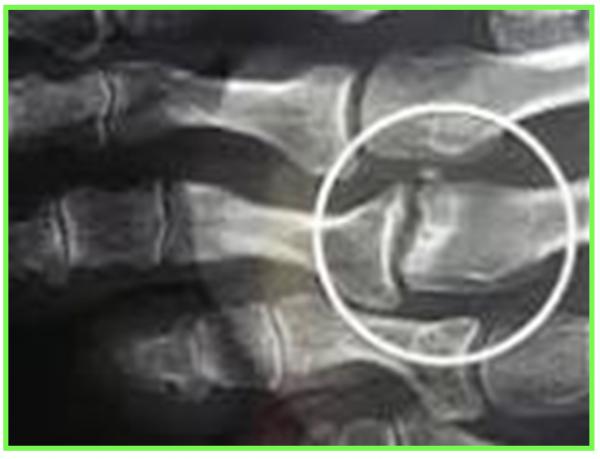

Le Syndrome du 2ème rayon est un syndrome douloureux dû à une surcharge mécanique sur l’articulation métatarso-phalangienne du 2éme orteil.

L’évolution se fera par la suite vers une déformation progressive du 2éme orteil

En fonction de l’importance de la lésion de la plaque plantaire (fissure simple ou complexe, déchirure), cela crée une déviation de l’orteil, perte d’appui, chevauchement d’orteils, apparition d’une « griffe », dislocation articulaire métatarso-phalangienne.

IRM : Bursite , rupture de la plaque plantaire